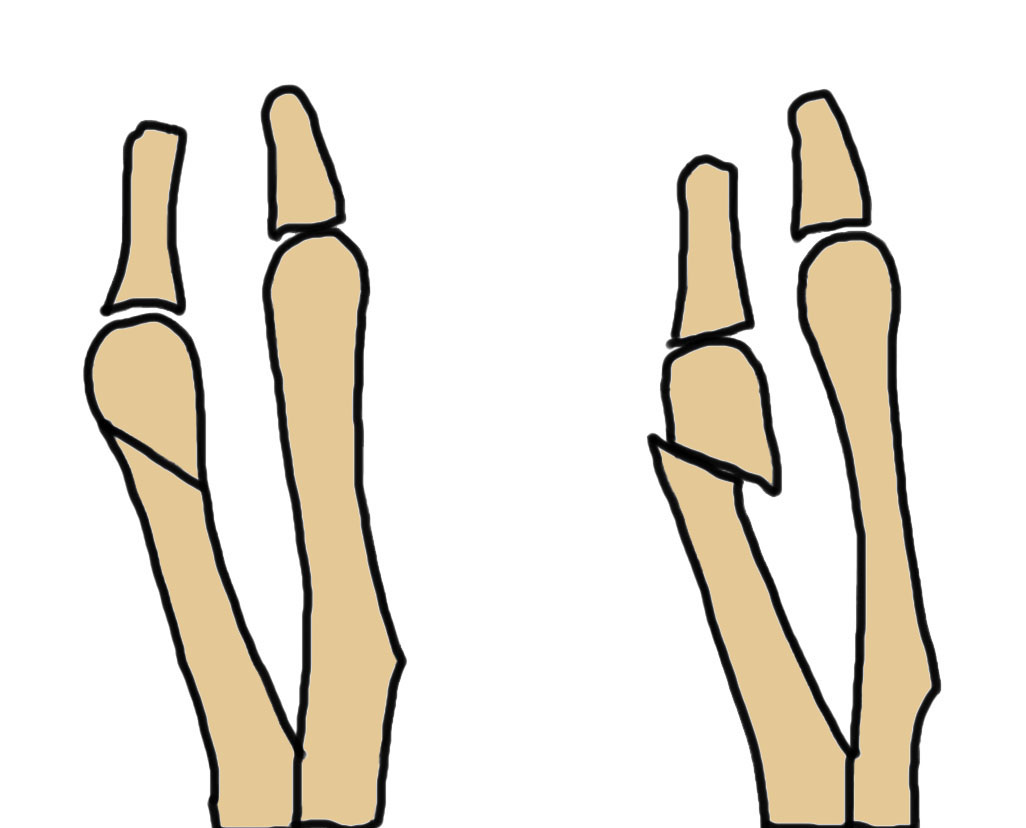

Osteotomy

Distal

- Weil distal sliding osteotomy

- Chevron osteotomy

Proximal

- Coughlin sliding oblique midshaft osteotomy

- proximal medial closing wedge osteotomy

- Scarfette osteotomy

| Weil | Chevron | Coughlin | Medial closing wedge | Scarfette |